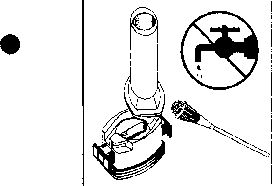

- İNFLACORT kapsülü inhalasyon cihazı ile nasıl kullanacağınızı öğrenmek için şekillerle gösterilen talimatları takip ediniz.

- Cihazı ağızlık yukarı doğru bakacak şekilde dik olarak tutunuz.

- Kenarlardaki iki kulakçığa (düğmelere) aynı anda ve sadece bir kez sıkıca basarak kapsülü deliniz.

- Ağızlığı ağzınıza yerleştiriniz ve başınızı hafifçe geriye doğru eğiniz.

- Dudaklarınızla ağızlığın etrafım sıkıca sarınız.

- Hızlı, duraksamadan ve alabildiğiniz kadar derin bir nefes alınız.

1. Kapağı çekip çıkarınız

2. Kapsül bölmesini açınız.

İnhalerin tabanını sıkıca tutup, açmak için ağızlığı üzerinde yer alan ok işareti yönünde döndürünüz.

3. Parmaklarınızın tamamen kuru olduğundan emin olunuz. Blisterden bir kapsül çıkarınız ve bu kapsülü cihazın tabanındaki kapsül bölmesine yatık olarak yerleştiriniz. Kapsülü, kullanmadan hemen önce blisterden çıkarmanız önemlidir.

ÖNEMLİ: Kapsülü ağızlığın İçerisinekoymayınız!

4. “Tık” sesini duyana kadar ağızlığı ok yönünün tersine döndürerek kapsül bölmesini kapatınız.

5. Tozu kapsülden serbestlemek için:

Not: Kapsül bu aşamada parçalanabilir ve küçük jelatin parçacıkları ağzınıza ya da boğazınıza gelebilir. Fakat jelatin yenilebilir nitelikte olduğu için zararlı değildir._ 6. Nefesinizi dışarıya olabildiğince veriniz.

7. İlacı derin bir şekilde hava yollarınıza çekmek

için:

Not: Kapsülün, kapsül bölmesinin üzerindeki alanda dönmesine bağlı olarak bir vızıldama sesi

duymalısınız. Eğer bu vızıldama sesini duymazsanız, kapsül bölmesini açınız ve kapsülün, kapsül bölmesinde sıkışıp sıkışmadığını kontrol ediniz. Daha sonra 7. basamağı tekrarlayınız. Kapsülü sıkıştığı yerden kurtarmak için düğmelere tekrar BASMAYINIZ.

8. Cihazın içerisinden nefes aldıktan sonra, nefesinizi olabildiğince tutunuz ve cihazı ağızdan çıkarınız. Sonra burnunuzdan nefes veriniz. Kapsül bölmesini açınız ve kapsülde toz kalıp kalmadığını kontrol ediniz. Eğer kalmış ise 6-8. işlemleri tekrarlayınız

9. Tüm tozu kullandıktan sonra kapsül bölmesini açınız (Bkz. basamak 2). Boş kapsülü çıkarınız ve içeride kalan tozları temizlemek için kuru bir kağıt mendil ya da yumuşak bir fırça kullanınız.

Not: İnhalasyon cihazını temizlemek için SU KULLANMAYINIZ.

10. Önce ağızlığı, ardından kapağı kapatınız.